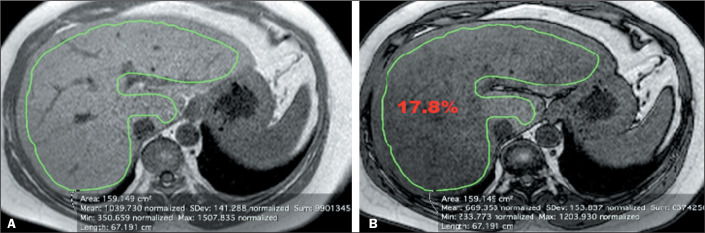

目的评估量化肝脂肪变性的三种不同测量策略,并研究同质性和异质性肝脂肪变性之间的差异:通过磁共振成像检查进行回顾性研究。我们在两个匹配组:同质性和异质性脂肪变性中评估了量化肝脂肪变性的三种不同策略。在所有测试中,我们都将 P < 0.05 视为显著性水平:结果:在异质性脂肪变性组中,用 1 平方厘米的感兴趣区(ROI)来测量改变最严重区域的信号强度的策略在量化上有显著差异,而轴切片中四个 1 平方厘米感兴趣区或代表性目标区域的平均值没有显著差异。在弥漫性肝脂肪变性中,所使用的任何策略都没有明显差异。类内相关系数介于 0.96 和 0.99 之间,95% 置信区间为 0.93-0.99:仅使用一个 ROI 进行磁共振成像脂肪肝量化的代表性较差,尤其是在异质性脂肪肝中。四个 ROI 的平均值策略与实质组织代表性分割区域策略之间没有明显差异。

Results: In heterogeneous steatosis group, the strategy with a region of interest (ROI) of 1 cm2 to measure the signal intensity in the most altered area showed significant variations in the quantification, while the average of four ROIs of 1 cm2 or representative target area in axial section did not vary significant. In diffuse hepatic steatosis, any strategy used showed no significant difference. The intraclass correlation coefficient ranged between 0.96 and 0.99, with 95% confidence interval of 0.93-0.99.

Conclusion: The quantification of fat liver by magnetic resonance imaging using only one ROI is less representative, especially in heterogeneous steatosis. There was no significant difference between the average of four ROIs strategy and the strategy of representative segmentation area of parenchyma.